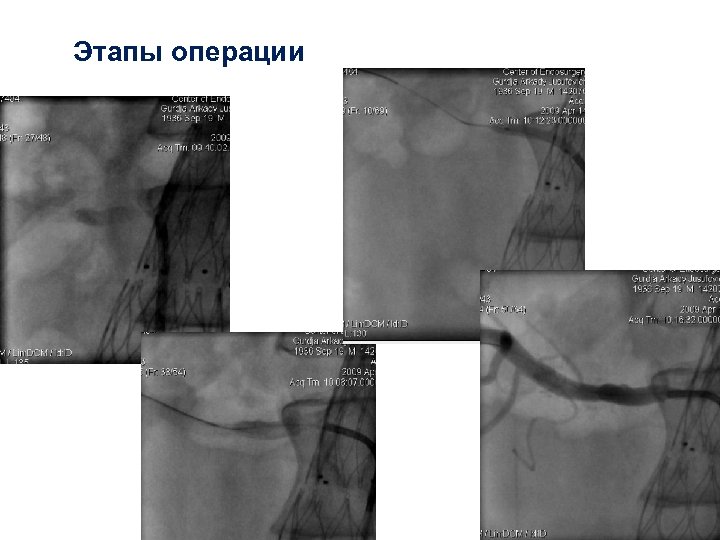

“Этапы операции

“Этапы операции

Этапы операции

Этапы операции